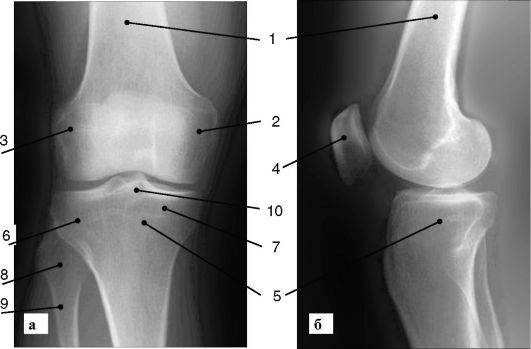

Рентгенограммы здорового коленного сустава: полезные советы и фотографии

На этой странице вы найдете подборку фотографий рентгенограмм здорового коленного сустава, а также полезные советы, которые помогут вам лучше понять, как выглядит нормальное состояние этого важного сустава.

Нормальная рентген-анатомия коленного сустава